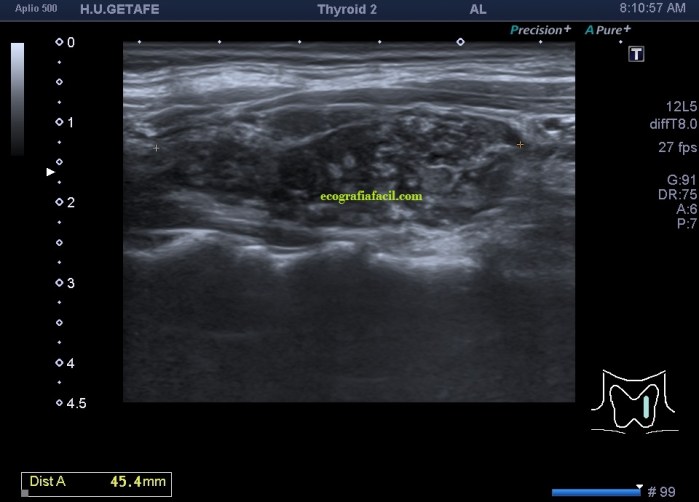

De la imagen 1 a 7 el protocolo habitual, el estudio particular del nódulo con medidas y aplicación del doppler demuestra el aspecto típico del Caballero Blanco.

Resumen de las imágenes que has visto en el caso de hoy:

- Hipoecogenicidad del parénquima

- Heteroecogenicidad

- Múltiples nódulos hipoecoicos muy pequeños

- Doppler Color y Doppler Power aumentado de tamaño en el nódulo

Este es el aspecto ecográfico descrito anteriormente de la patología que habitualmente puede albergar el nódulo del que trata hoy el post y que no es otra que la de la Tiroiditis de Hashimoto.

El Caballero blanco, recibe el nombre debido a su semiología hiperecogénica, homogénea y solitaria circunscrito en la patología referida con anterioridad, puede aparecer en esta patología de forma benigna o degenerar en otro tipo de patología a formas malignas como el linfoma tiroideo.